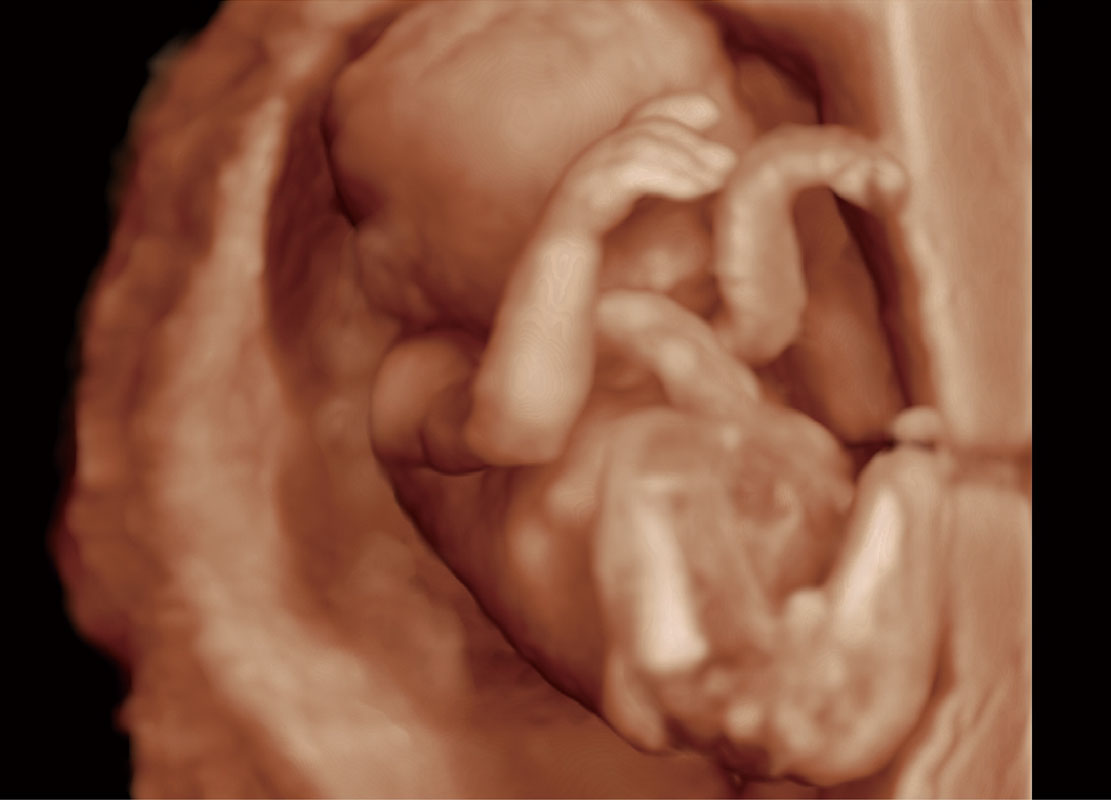

P60在胎兒早孕期超聲篩查中為您帶來優(yōu)異的圖像質(zhì)量。

高分辨率容積成像-早孕胎兒

光影成像-孕囊